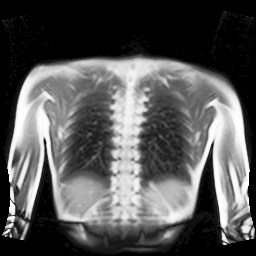

Refer to captionRefer to captionRefer to captionRefer to captionRefer to captionRefer to captionRefer to captionRefer to captionRefer to captionRefer to captionRefer to captionRefer to captionRefer to captionRefer to caption

Figure 5: Maximum inspiration (top row) and maximum expiration (bottom row) for different slice positions of one patient from back to front.

For a complete chest volume coverage, the lung is scanned at different slice positions as shown in Figure 5. At each slice position, a dynamic 2D+t image series with 140 images is acquired. For the further analysis of the image data, all images of one slice position need to be spatially aligned. We choose the image which is closest to the mean respiratory cycle as fixed image of the series. The other images of the series are then registered to this image. Our data set consists of 48 lung acquisitions of 42 different patients. Each lung scan contains between 7 and 14 slices. We used the data of 34 patients for the training set, 4 for the evaluation set, and 4 for the test set.